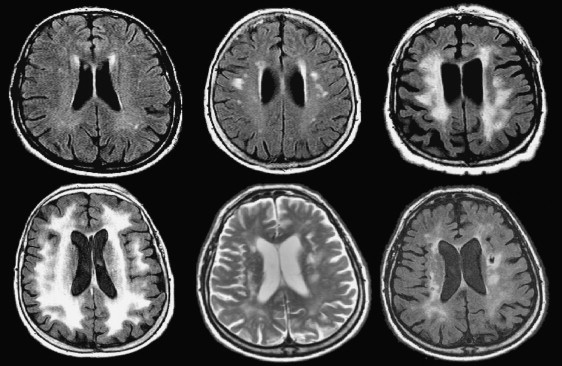

Vascular Dementia | Radiology Reference Article | Radiopaedia.org

radiopaedia.org

radiopaedia.org

Dementia, MRI Scans - Stock Image - M140/0435 - Science Photo Library

Representative Brain MRI Of Dementia Patients. A Patient A Was

www.researchgate.net

www.researchgate.net

dementia mri patients diagnosed publication vascular atrophy